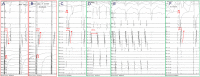

Results: Mitral isthmus block was successfully achieved in 69/72 patients (95.6%). Five patients developed PMF after confirming MI block. In these patients, high-density mapping during the PMF showed a breakthrough in MI with extremely low impulse conduction velocity (CV). In contrast, in usual PMF circuits that occurred after AF ablation, the lowest CV of the reentrant circuit was of significantly higher value (0.07 ± 0.02 m/s vs 0.25 ± 0.07 m/s, respectively; P < .001). Patients presented with clinical AT had better prognosis in maintaining sinus rhythm after MI ablation compared with patients presented with AF.